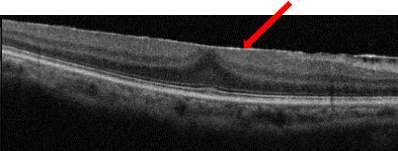

眼の中には硝子体という、水晶体と網膜の間の空間を満たすゼリー状の物質でが存在します。加齢とともに硝子体が液体に変化し網膜から剥がれます。(後部硝子体剥離)(図1)後部硝子体剥離が起こったとき、硝子体と黄斑の癒着が強いとうまくはがれず、黄斑に残った硝子体を基にして、黄斑前膜ができます。(図2)